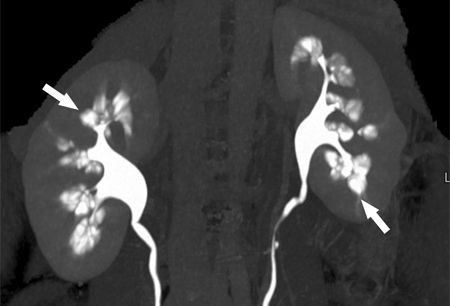

The medullary sponge kidney is characterized by cystic dilatations of the collecting ducts. Patients may present with hematuria, UTI, nephrolithiasis, or maybe completely asymptomatic. It is thought to be associated with hyperparathyroidism and parathyroid adenoma. Diagnosis is confirmed by an intravenous pyelogram. There is no specific treatment for the medullary sponge kidney. However, prevention of stone formation and treatment of associated recurrent UTIs should be done.